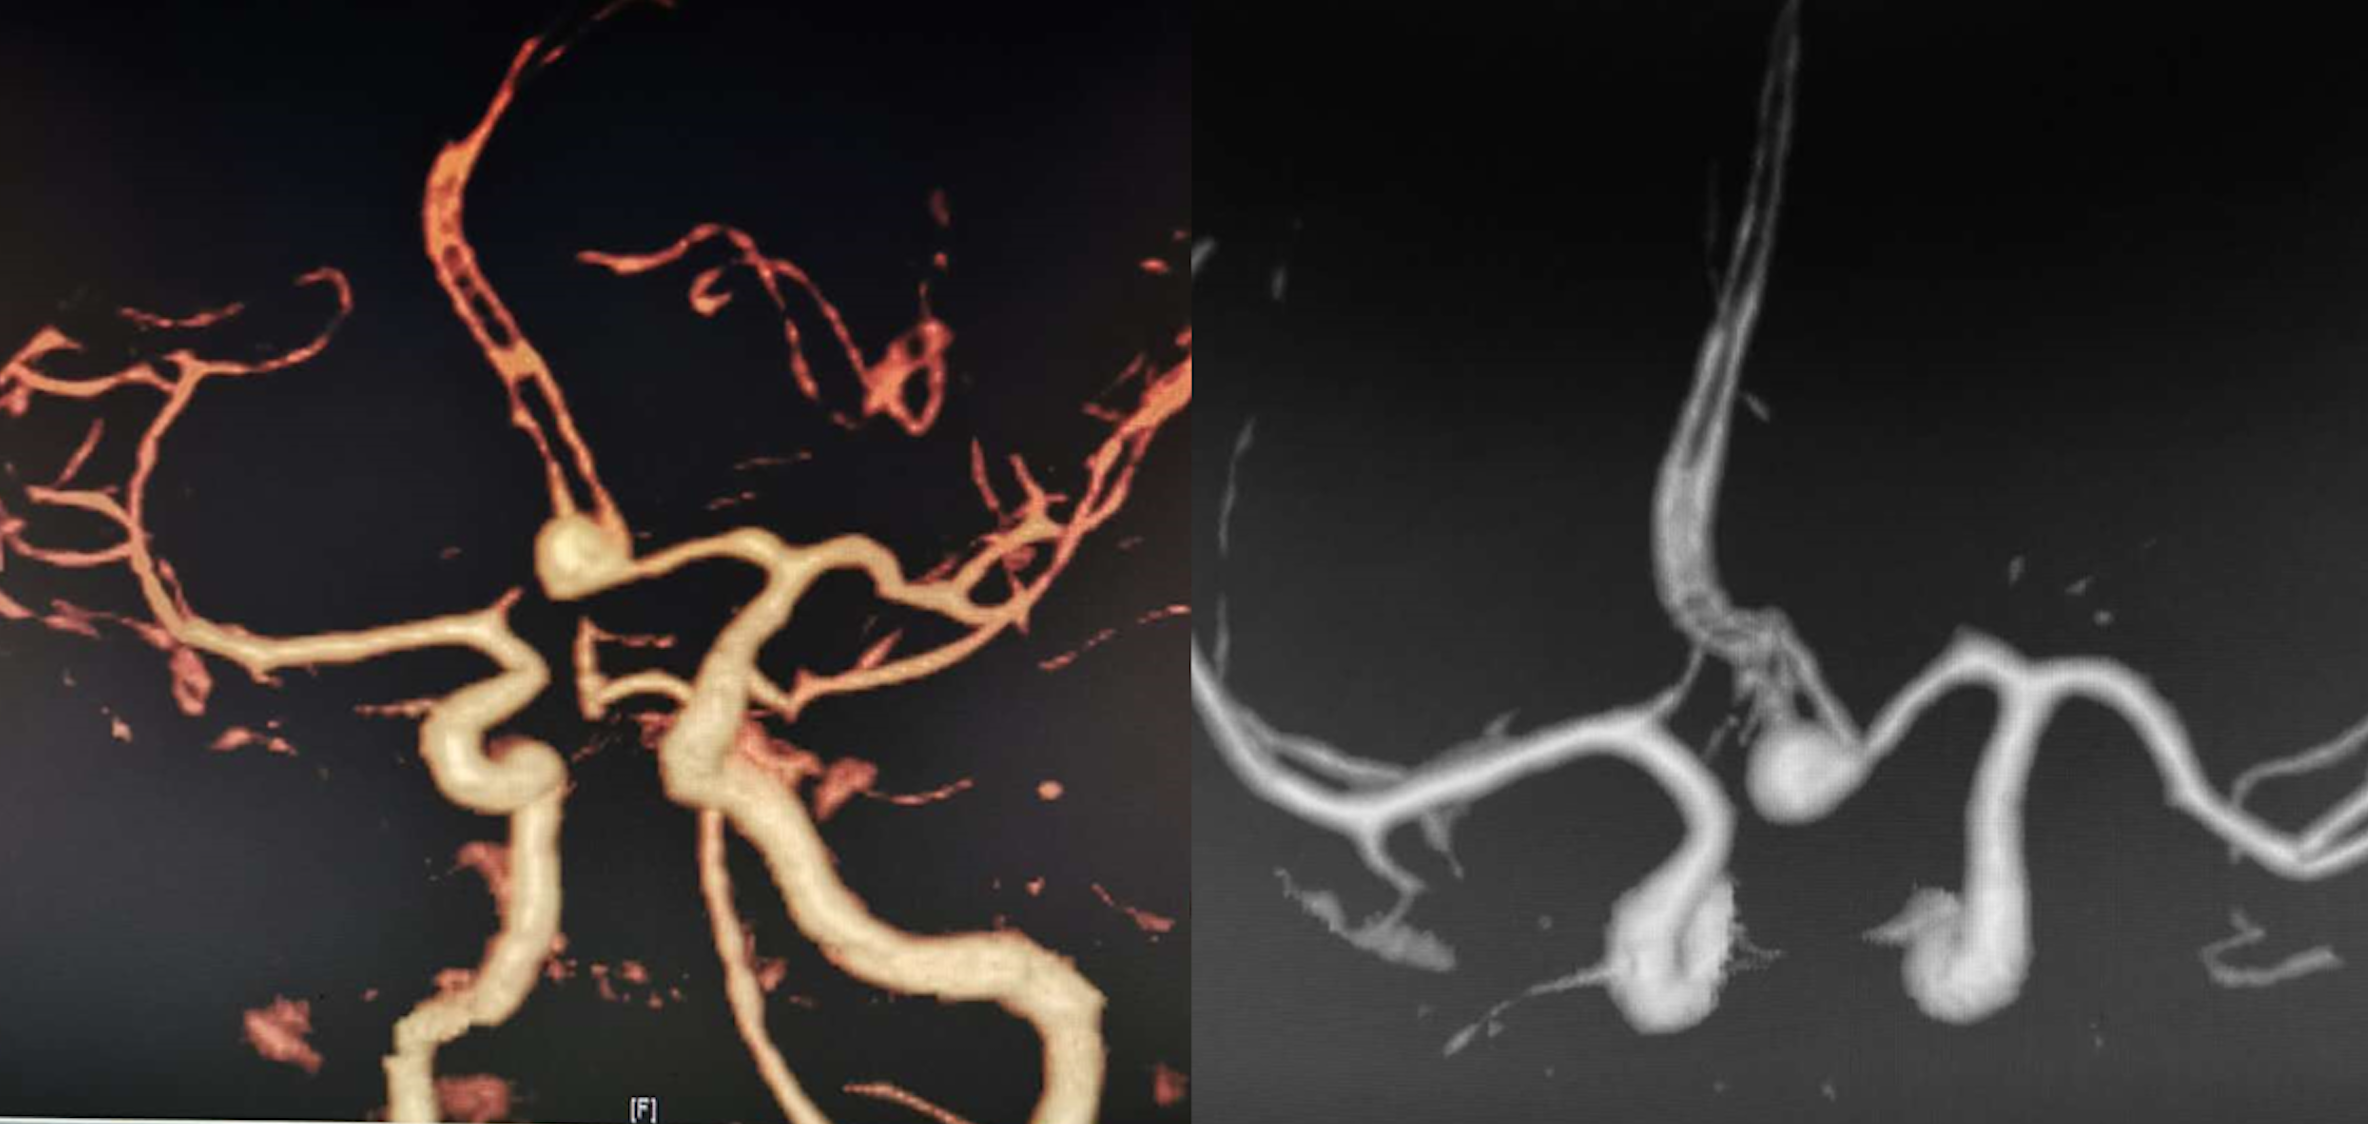

术前影像

颅内动脉瘤的精准夹闭